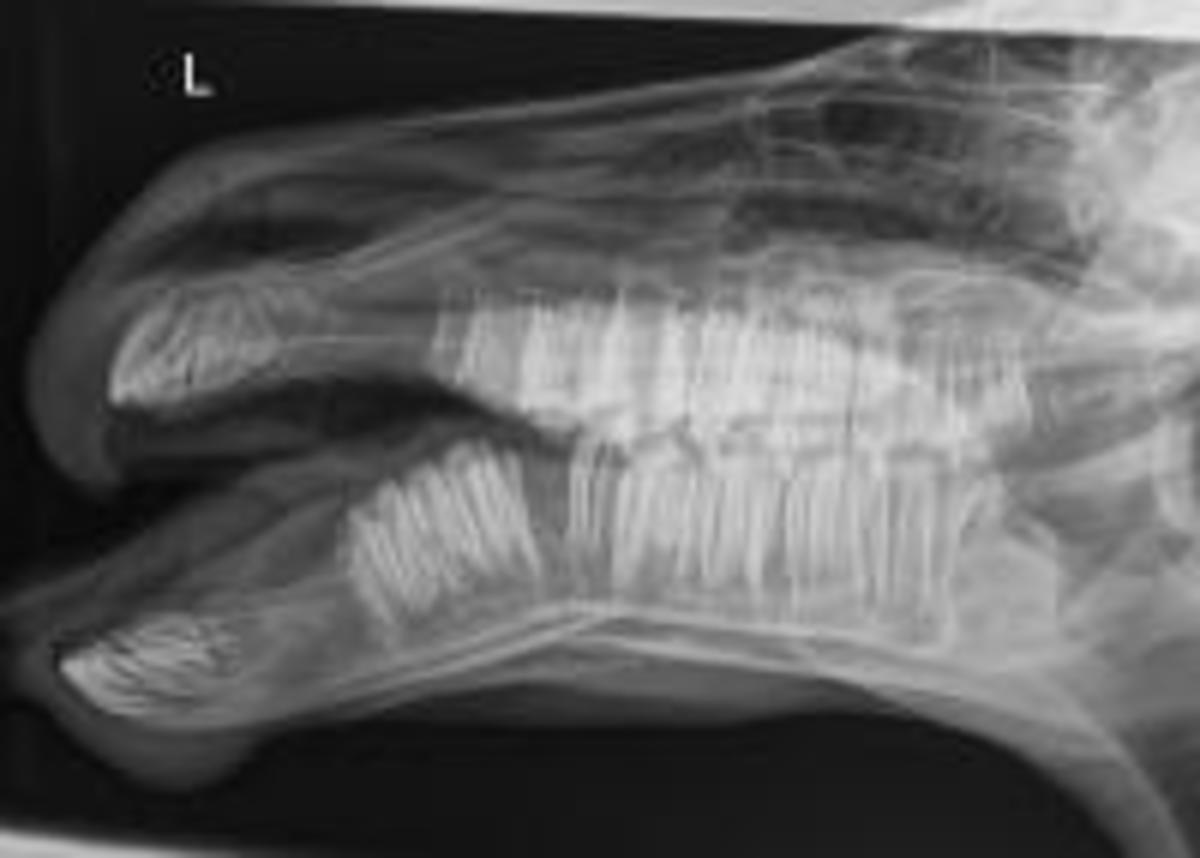

Dislocated Jaw X Ray Collection 2022 Dislocated Jaw X Ray Collection 2022

Dislocated Jaw X Ray

Learning Radiology - Dislocated, Mandible, Mandibular, Dislocation Dislocated Jaw: Symptoms and Treatment Bilateral temporomandibular joint dislocation | Radiology Case ... Pretreatment X-ray showing the anterior dislocation. | Download ... Learning Radiology - Dislocated, Mandible, Mandibular, Dislocation Dislocated Jaw X Ray